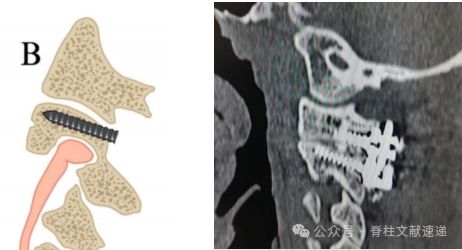

(B) 对于1型HRVA,可以接受高进针点(峡部顶端)的经椎弓根螺钉或导航辅助的螺钉。

进钉点明显上移的C2椎弓根螺钉,适用于上图所示的情况。可以得到坚强的固定。

如下图所示。该置钉技术距离C1螺钉非常近。可能会存在钉尾打架的情况,安装不上连接棒。此螺钉技术更适合枕颈固定。